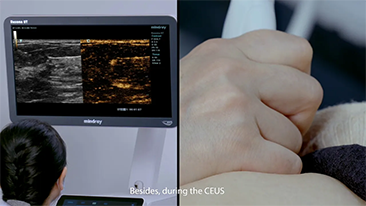

Solusi Pencitraan Umum Resona dari Mindray membantu para dokter mewujudkan diagnosis dan hasil pengobatan yang lebih akurat dan efisien melalui pemerik aplikasi subdivisi yang komprehensif dan alat bantu aplikasi klinis yang efisien.

Lingkungan medis saat ini telah menjadi lebih kompleks, dengan peningkatan jumlah kasus yang sulit dan beban kerja.